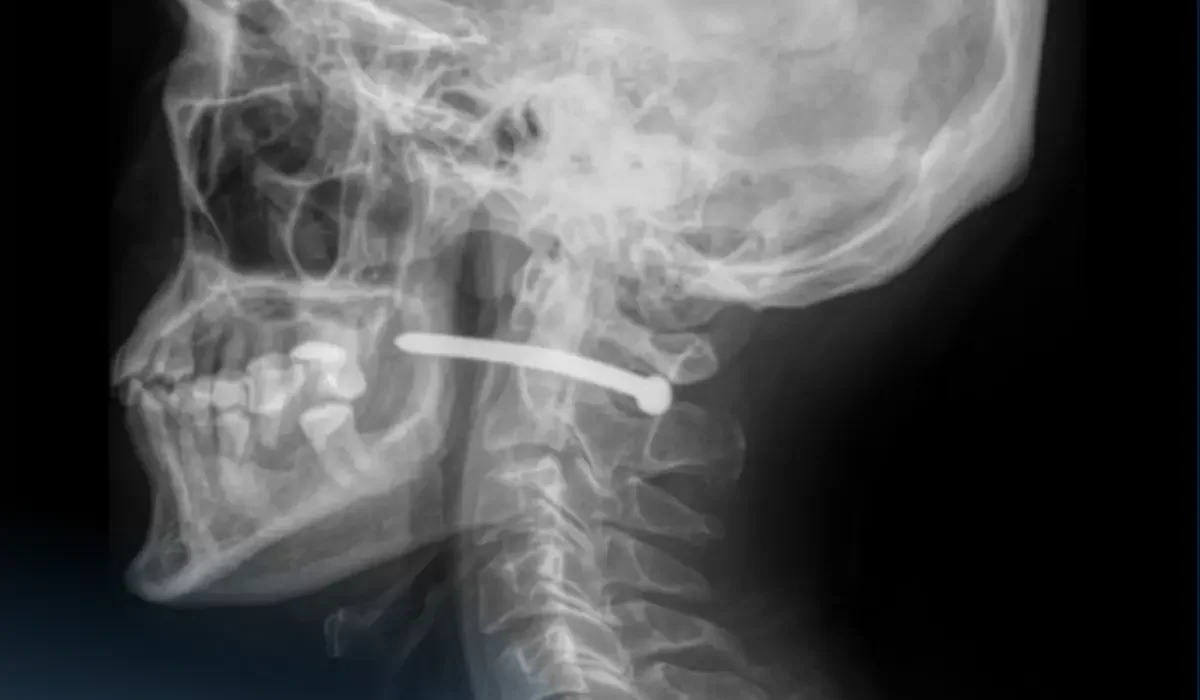

Петропавл тұрғыны мойнына шеге қадап алған

Петропавлда дәрігерлер жөндеу жұмыстары кезінде мойнына шеге қадалып қалған ер адамды ажалдан арашалап, деп хабарлайды  Skifnews.kz ақпарат порталы.

Көп бейінді қалалық жедел медициналық жәрдем ауруханасына 51 жасар ер адам құлақ маңындағы жарамен көмекке жүгінген. Ол жөндеу жұмыстары кезінде шегеге арналған пневматикалық құралдың шегесінен жарақат алған.

«Рентген-зерттеуден кейін шегенің омыртқаның мойын бөлігінен өткені анықталды. Ер адамның көрер жарығы бар екен – өміріне маңызды органдары зақым алған жоқ», - деп жазды аурухананың баспасөз қызметі.

Жақсүйек-бет хирургтары жарадан шегені алып, қарап, жараны өңдеді. Жара тігіліп, стерильді таңғыш салынғаннан кейін науқасқа ұсыныстар беріліп, үйіне жіберілді.

«Мойын тұзына жарақат алу өте қауіпті – мойынның маңайынан үлкен тамырлар, нервтер, тыныс алу жолдары және жұлын өтеді. Тіпті кішкене ғана зақым алудың салдары ауыр болуы мүмкін», - деп ескертті дәрігерлер.